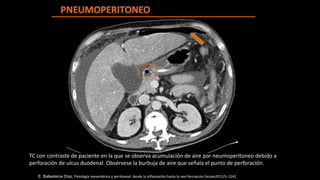

TC con contraste de paciente en la que se observa acumulación de aire por neumoperitoneo debido a

perforación de ulcus duodenal. Obsérvese la burbuja de aire que señala el punto de perforación.

E. Ballesteros Díaz, Patología mesentérica y peritoneal: desde la inflamación hasta la neo formación Seram2012/S-1242